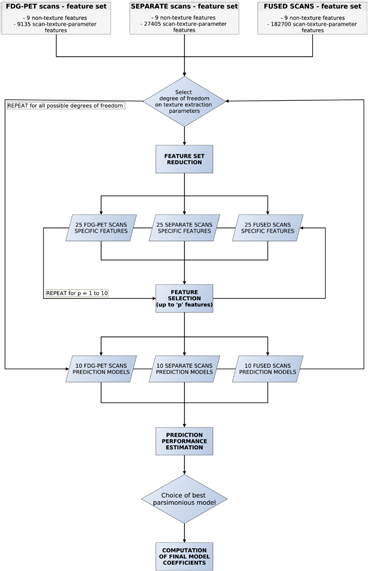

Considering the full set of texture extraction parameters of Global features and higher-order texture features (GLCM, GLRLM, GLSZM and NGTDM), a total of 27 405 and 182 700 scan-texture-parameter combinations were computed in this work for separate and fused scans, respectively. Figure 4 presents a summary of the workflow of extraction of texture features.

Figure 4. Workflow of extraction of texture features.

Prediction models were constructed for three different types of initial feature sets: (i) 9 non-texture features + 9 135 FDG-PET scan-texture-parameter features; (ii) 9 non-texture features + 27 405 separate FDG-PET and MRI scan-texture-parameter features; and (iii) 9 non-texture features + 182 700 fused FDG-PET/MRI scan-texture-parameter features. First, feature set reduction was performed through a stepwise forward feature selection scheme in order to create reduced feature sets containing 25 different scan-texture features from larger initial sets, a procedure carried out using the Gain equation:

Figure 5 summarizes the workflow of multivariable analysis.

Figure 5. Workflow of multivariable analysis.